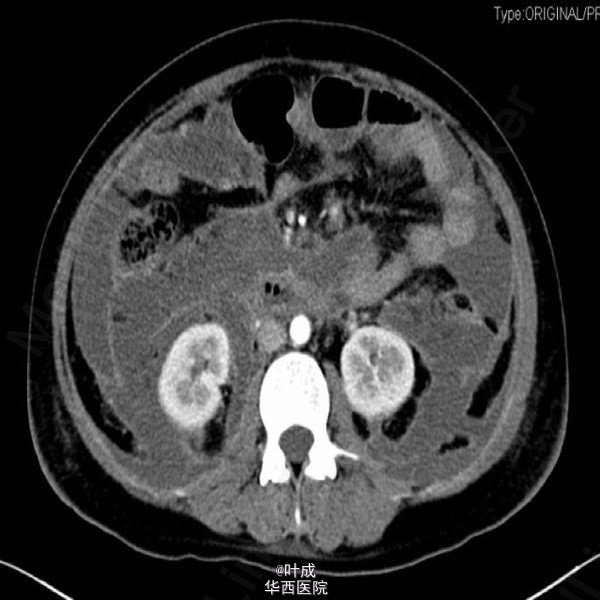

患者女,39岁,因“腹痛2天”入院。患者既往否认胆道疾病病史。入院查体:T:36.5oC,P:130次/分,R:28次/分,BP:135/85mmHg,BMI=25kg/m2。心肺查体无特殊。腹部饱满,全腹肌紧张,上腹压痛,无反跳痛,腹部未触及包块。肝脾肋下未触及。辅助检查:血清淀粉酶 827 IU/L,脂肪酶 720IU/L;血常规:血红蛋白 193g/L,白细胞 8.02*10^9/L,中性粒 80.2%;血甘油三酯 20.33mmol/L,胆固醇 10.80mmol/L;血钙 1.54mmol/L;胸腹部平扫CT示:胰腺肿胀,实质密度不均匀减低,周围脂肪间隙模糊,散在渗出积液影,腹、盆腔、双侧胸腔积液,肺部感染(图2);腹部超声提示脂肪肝,肝内外胆管未见扩张。入院APACHE II评分13分。入院诊断:急性胰腺炎(重度 高脂血症型),肺部感染)。入院后予禁食,控制补液,奥曲肽抑制胰腺分泌,埃索美拉唑抑酸,导泻,加贝酯抑制胰酶,哌拉西林舒巴坦抗感染,维持电解质平衡,补充丙氨酰谷氨酰胺等治疗。患者腹痛症状逐渐缓解,每日出入量大体平衡,但腹胀、气紧症状逐渐加重,沟通后予无创呼吸机辅助通气(中途尝试停用未遂,共使用13天),期间血气分析血氧分压变化见图1(期间存在误采静脉血可能)。患者气紧较前缓解,仍有腹胀,纳差,肛门排期排便可,复查腹部增强CT:胰腺未见明显坏死灶,与之前比较,腹腔积液增多,部分包裹,炎症累及区域脂肪密度降低。双侧胸腔少量积液并双下肺局部肺不张(图3-4);复查甘油三酯 3.63 mmol/L,血清白蛋白>40g/L。治疗上逐步加强肠内营养,予螺内酯利尿,患者腹胀较前有所缓解。